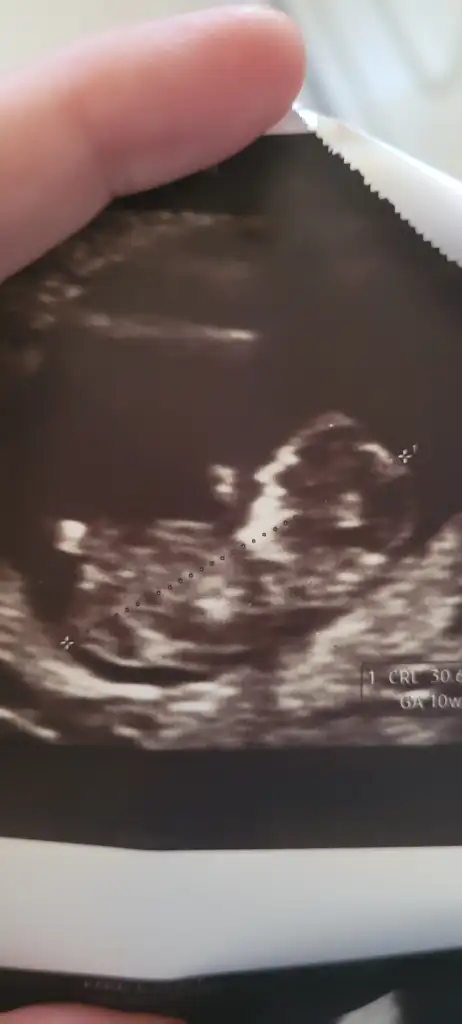

12 haftaliktiBu kac haftalıkken

Hm küçükmüs ya benim attığım 15haftalik sana 12de erkekmi dediler12 haftalikti

Doktor 11 haftada yuzde70 kiz demisti 12de erkek bu dediHm küçükmüs ya benim attığım 15haftalik sana 12de erkekmi dediler

Baya erken zamanda kız demişya banada 14.haftada söyledi kız diye çizgileri gösterdi kız genital bolgesi diye smdi iki çizgi arasından pipi çıkmasını bekliyoruz böyle bişey mumkunmuDoktor 11 haftada yuzde70 kiz demisti 12de erkek bu dedi

Bu usgyi vermisti tabi ben o zamanlar nub falan bilmiyordum bu sene ogrendim bakmistim cidden de organi belli oluyor 12de bile